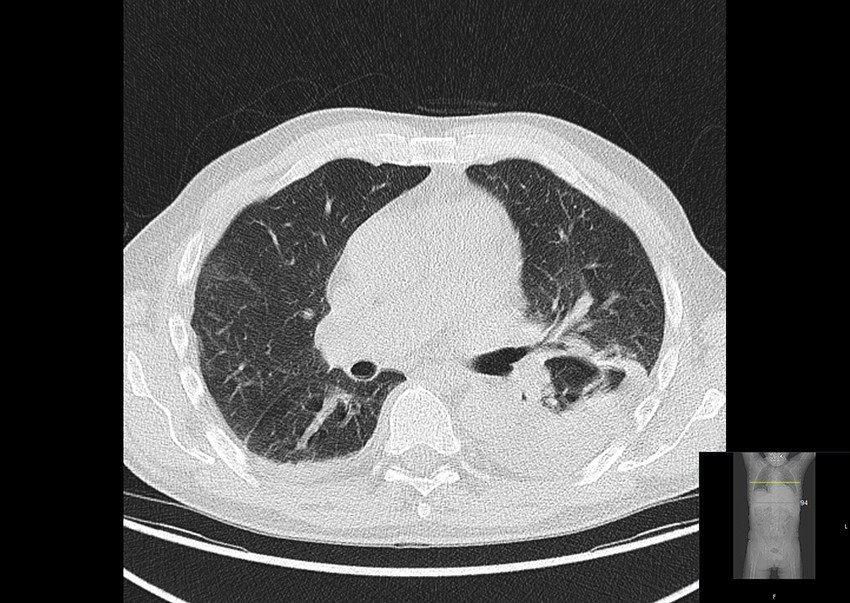

PET-CT scanning with 18F-fluorodeoxyglucose (18F-FDG) performed on admission showed increased uptake of 18F-fluorodeoxyglucose in the thoracic aorta, aortic arch branches and pericardium (Figure 1).

There was also increased uptake of 18F-fluorodeoxyglucose in bone marrow and lymph nodes, which were considered to be reactive changes. In addition, an infiltrate in the lower lobe of the left lung and pleural effusion were also found (Figure 2).